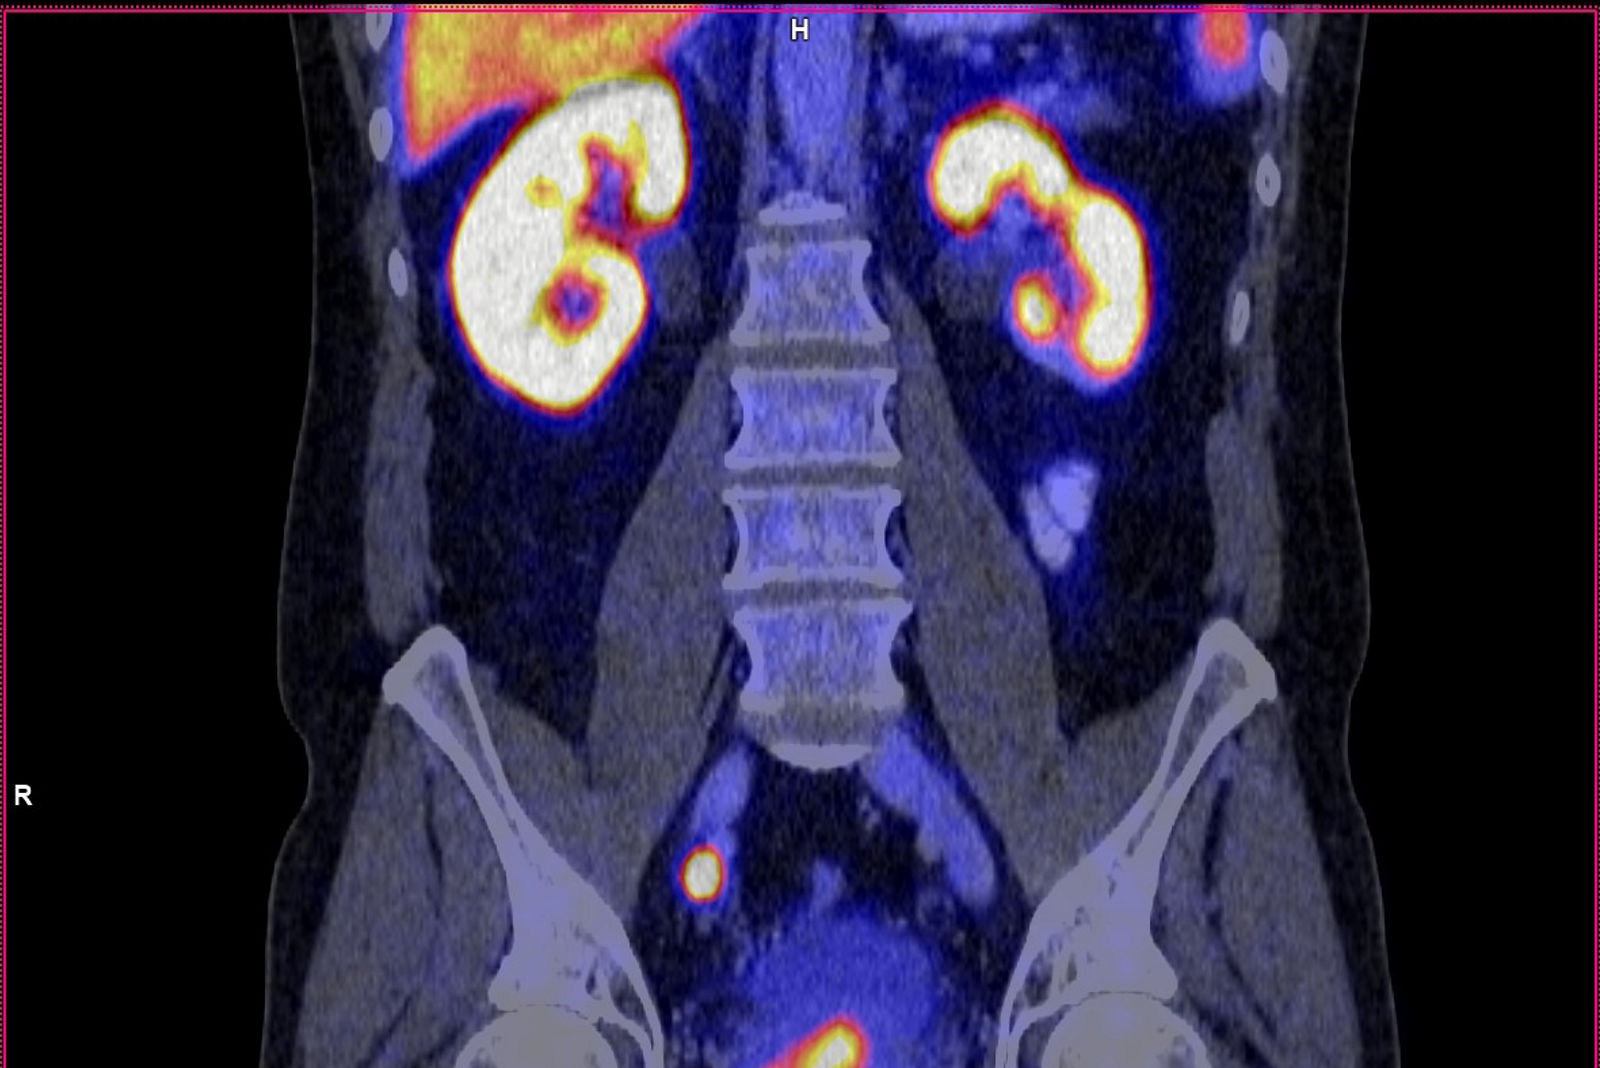

Die PET stellt durch den Einsatz schwach radioaktiver Substanzen unterschiedliche Stoffwechselvorgänge dar, die durch die Kombination mit der CT dann genau anatomisch zugeordnet werden können. Dadurch wird insbesondere in der Onkologie eine präzise und rasche Lokalisation von Tumorgewebe (Primärtumoren oder auch Metastasen) möglich und eine Therapie kann gezielter geplant werden. Manche Therapie wird durch die PET-CT in eine andere Richtung gelenkt, unnötige Therapien werden vermieden.

Der Schwerpunkt der PET-CT-Diagnostik liegt in der Onkologie. Aber auch bei neurologischen oder kardiologischen Fragenstellungen ist diese Form der Diagnostik von großer Bedeutung. Insbesondere bei der Diagnostik von Bronchialkarzinomen ist das Gerät sehr wertvoll. Seit 2010 ist die PET-CT-Untersuchung vor einem operativen Eingriff aufgrund von Lungenkrebs in den Behandlungsleitlinien festgeschrieben. Das Gerät stärkt somit die Leistungskraft des Bergischen Lungenzentrums. Um die fachübergreifende Nutzung des Gerätes zu vereinfachen und Behandlungen für den Patienten zu optimieren, sind die erzeugten Aufnahmen im gesamten System der Klinik nutzbar.